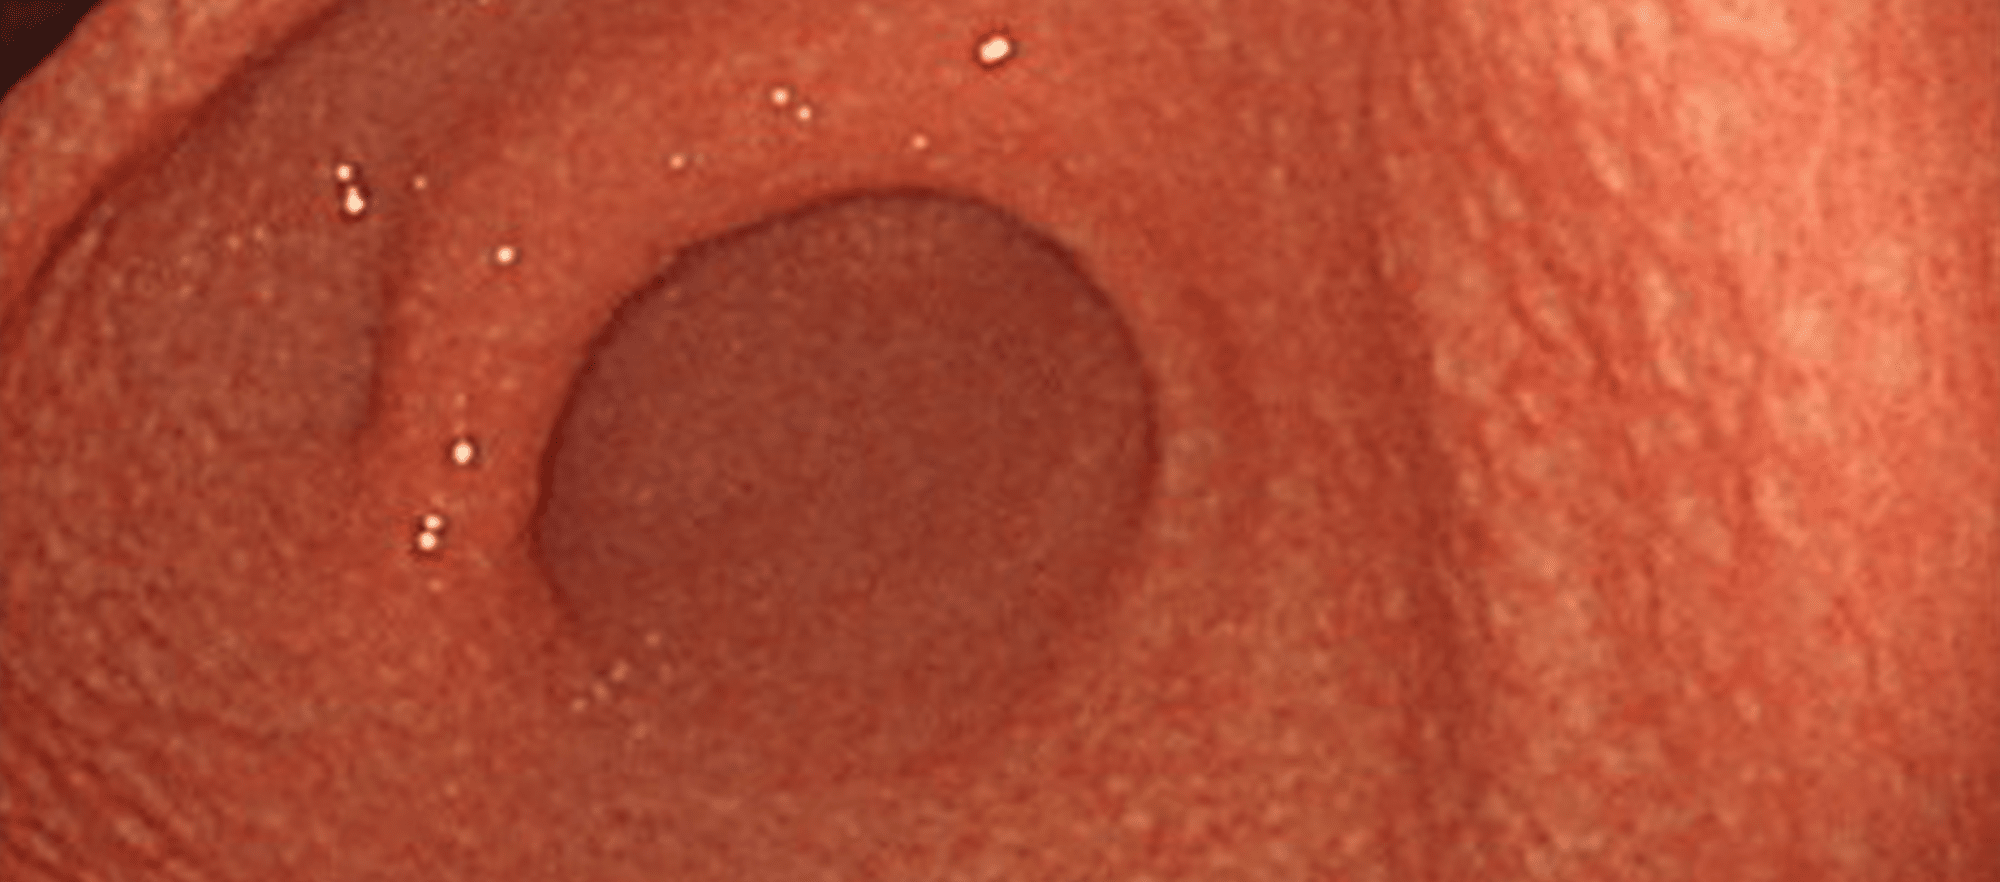

胃癌

胃痛や胃の不快感、食欲不振、体重減少などの症状がみられます。ピロリ菌の感染がある方ではリスクが高くなります。